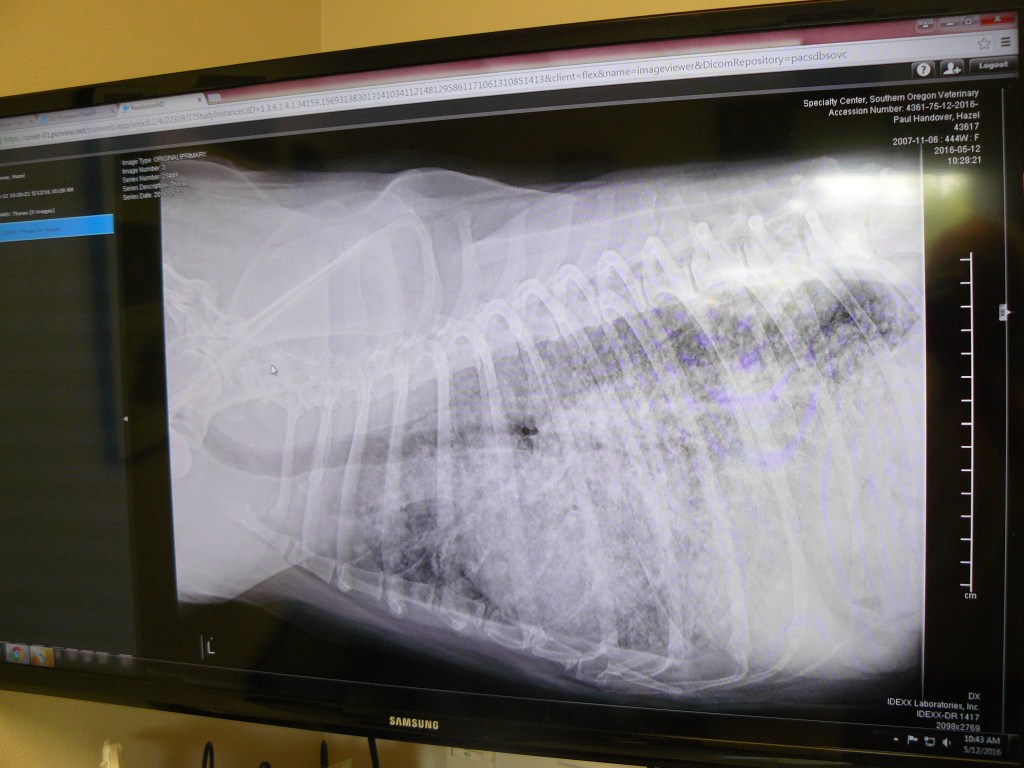

My photograph of the clinic's screen display.

My photograph of the clinic’s screen display.

This can be more readily seen if I publish the xray image of yesterday and the image taken on the 15th April; see below.

Xray image as of the morning of May 12th, 2016.

Despite not truly understanding these images both Jean and I quickly thought the top one, taken yesterday, showed a decline in Hazel’s lungs compared to the lower one, taken on the 15th April.